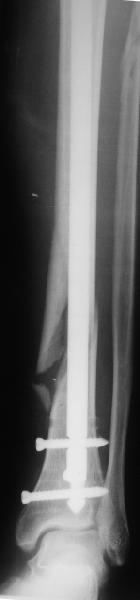

Вальгус, стержень в дистальный отломок введен не на оптимальную длину. Такой диастаз будет долго заполняться, что чревато переломом стержня по ближайшему отверстию.

Вальгус сам по себе небольшой. Имеется промежуточный отломок, который не притянулся, так как отломки до конца не растянули. Сейчас наверное стоит подождать 2-3 мес. и посмотреть как пойдет срастание.

На снимке сохранен небольшой вальгус, но имеется нормальная аппозиция медиального кортикального слоя и поэтому трудно согласится что здесь имеется неправильно фиксированный перелом. Для идеального сопоставления таких косых переломов надо открывать фокус травмы, но тогда меняется философия фиксации.

Все наши сомнения связаны с тем, что этих незначительных погрешностей (небольшой вальгус, неглубоко пробит гвоздь, мало запирающих винтов в

дистальном отломке) не одна, а несколько, и вместе они могут значительно осложнить дальнейшую жизнь пациенту. В нашей практике были подобные случаи, при которых после разрешения полной нагрузки либо начинала увеличиваться деформация, либо происходил перелом гвоздя по ближайшему отверстию. Кроме того, при диафизарных переломах, имея в арсенале надежный фиксатор, нет никакой необходимости вынуждать пациента ограничивать нагрузку на ногу в течении 2-3 месяцев.

Взвесив все <<за>> и <<против>>, мы приняли решение и выполнили реостеостинтез: выбили гвоздь до линии перелома, провели отклоняющую

спицу, забили обратно гвоздь и заблокировали внизу 3-мя винтами, вверху одним. Вся операция заняла меньше часа. Сегодня пациент ушел от нас домой с полной нагрузкой на ногу.